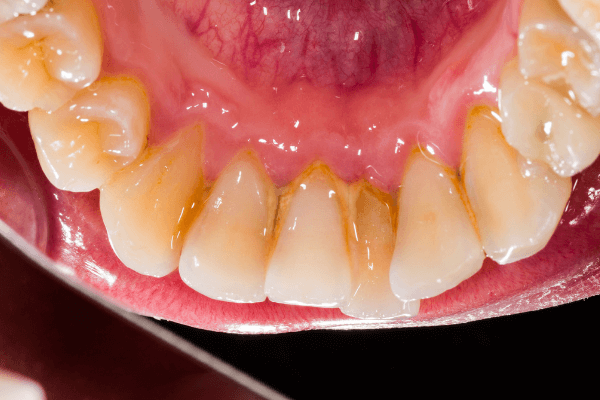

La parodontologie inclut l’évaluation parodontale avec examen clinique et radiographies pour mesurer la profondeur des poches parodontales, l’indice de plaque et de tartre, et vérifier la rétraction gingivale ou la mobilité dentaire.

Les procédures non chirurgicales comme le détartrage et le surfaçage radiculaire visent à nettoyer les racines des dents, tandis que la thérapie antimicrobienne aide à contrôler les infections.